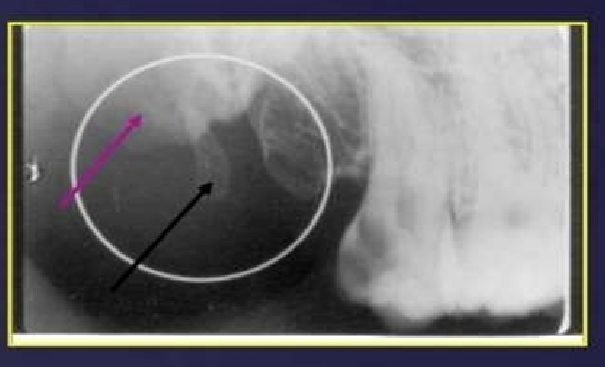

What has happened to the maxillary sinus in this image?

pneumatization - physiological process of expansion of sinus wall into surrounding bone , usually in an area where teeth have been lost prematurely